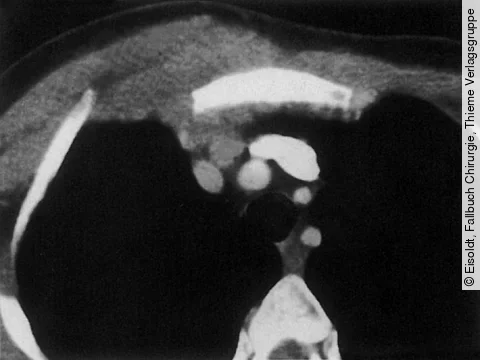

Quiz der Woche35-jähriger Sportler mit Muskelschwäche und Raumforderung im Mediastinum

CT des Hals und Thorax

Der junge, sportlich gebaute Mann fällt durch abnorm rasche Ermüdbarkeit auf.